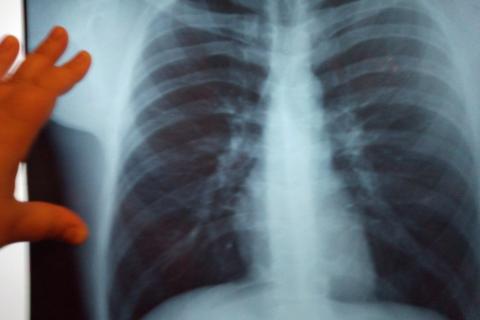

За первое полугодие 2022 года в Приангарье выявлено 704 новых случая заболевания туберкулезом, что на 4 больше, чем за аналогичный период 2021 года. В целом показатель заболеваемости туберкулезом в регионе составляет 59,9 случая на 100 000 населения области. В процентном соотношении заболеваемость увеличилась на 4,5 %.

Врачи убедительно просят - проходите своевременно флюорографическое обследование!